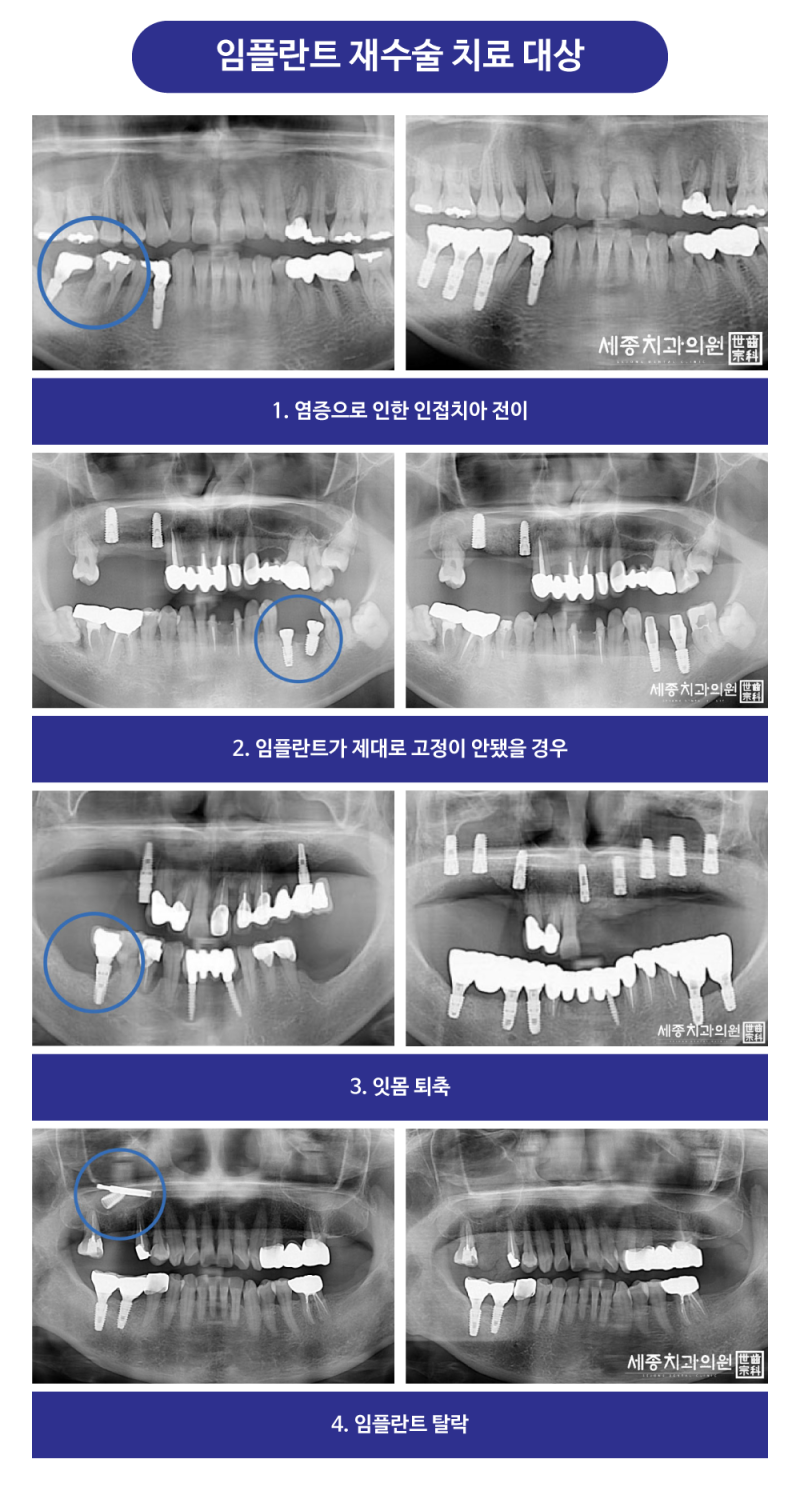

부산임플란트치과 세종치과 재수술 임플란트 환자의 상태는 적절하지 않은 위치에 임플란트가 식립되어 있고 앞니쪽은 너무 두꺼운 임플란트가 식립되었습니다.

그리고 높낮이도 맞지 않아서 뼈에 심어져 있어야 할 부분이 뼈에서 나와 있는 상태이기 때문에 기존 임플란트를 제거하기로 했습니다.

임플란트 재수술은 왜 필요한가요?임플란트가 흔들리거나 붓고 피가 나고 이상한 냄새가 나거나 제대로 씹히지 못할 때는 임플란트가 제대로 기능하지 않기 때문에 면밀한 검진과 진단을 통해 임플란트 재수술을 해야 합니다.